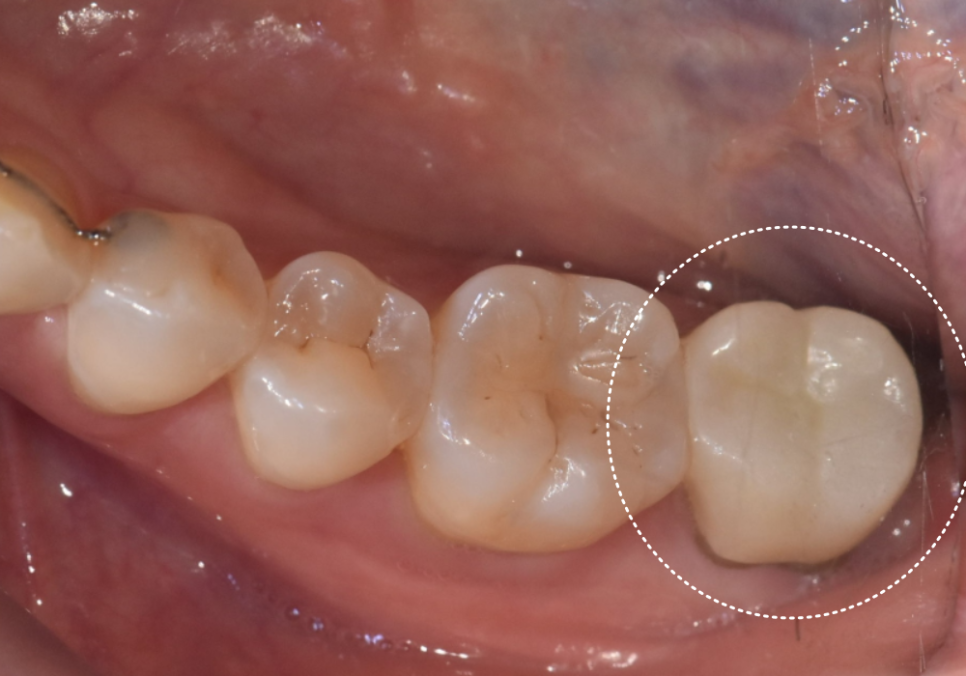

3개월 후, 잇몸 뼈와 임플란트가 하나처럼

단단히 붙은 것을 확인 뒤,

지르코니아로 맞춤 보철물까지

완벽하게 완성해 드렸습니다.^^

251015

2050508(전) 251015(후)